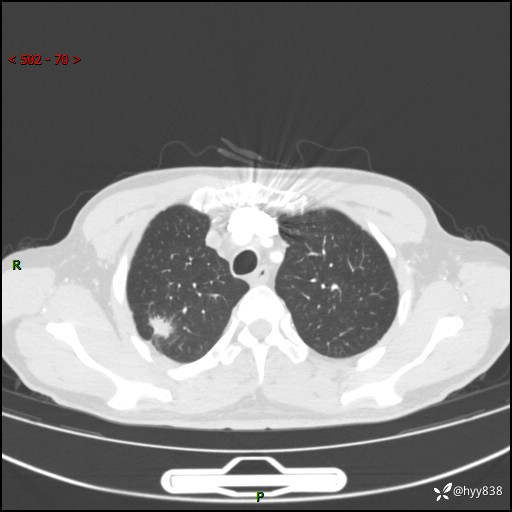

69岁/男,发现肺部病变6天。该有的征象都有,肉芽肿 VS 肿瘤,一念之间---(有结果)

主诉:发现肺部病变6天。

现病史:患者6天前于我院泌尿外科住院,住院期间行胸部CT检查,提示“肺部病变”,患者无畏寒、发热、盗汗、咳嗽、咳痰、咯血、胸痛、呼吸困难,无反酸、腹痛、腹泻、头痛、头晕等不适。未予特殊处理,现为进一步诊治,门诊以“肺肿物”收入我科。 患者本次起病以来,精神食欲尚可,大小便正常,体力及体重无明显变化。

胸部CT平扫+增强